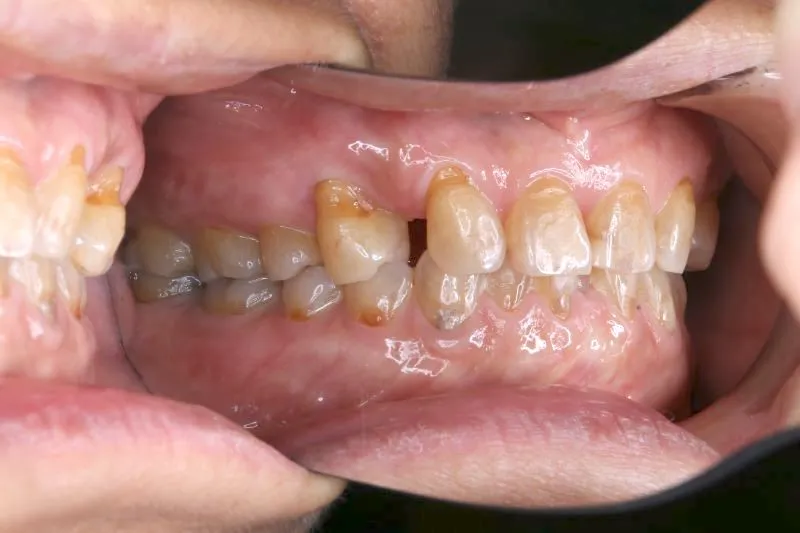

2.診断名あるいは主な症状 空隙歯列・先天性欠損歯

上の歯が2本足りないため上下のアーチが合わず、下の歯がガタガタになっています。

上下の幅をあわせ、噛み合わせから調整していきます。